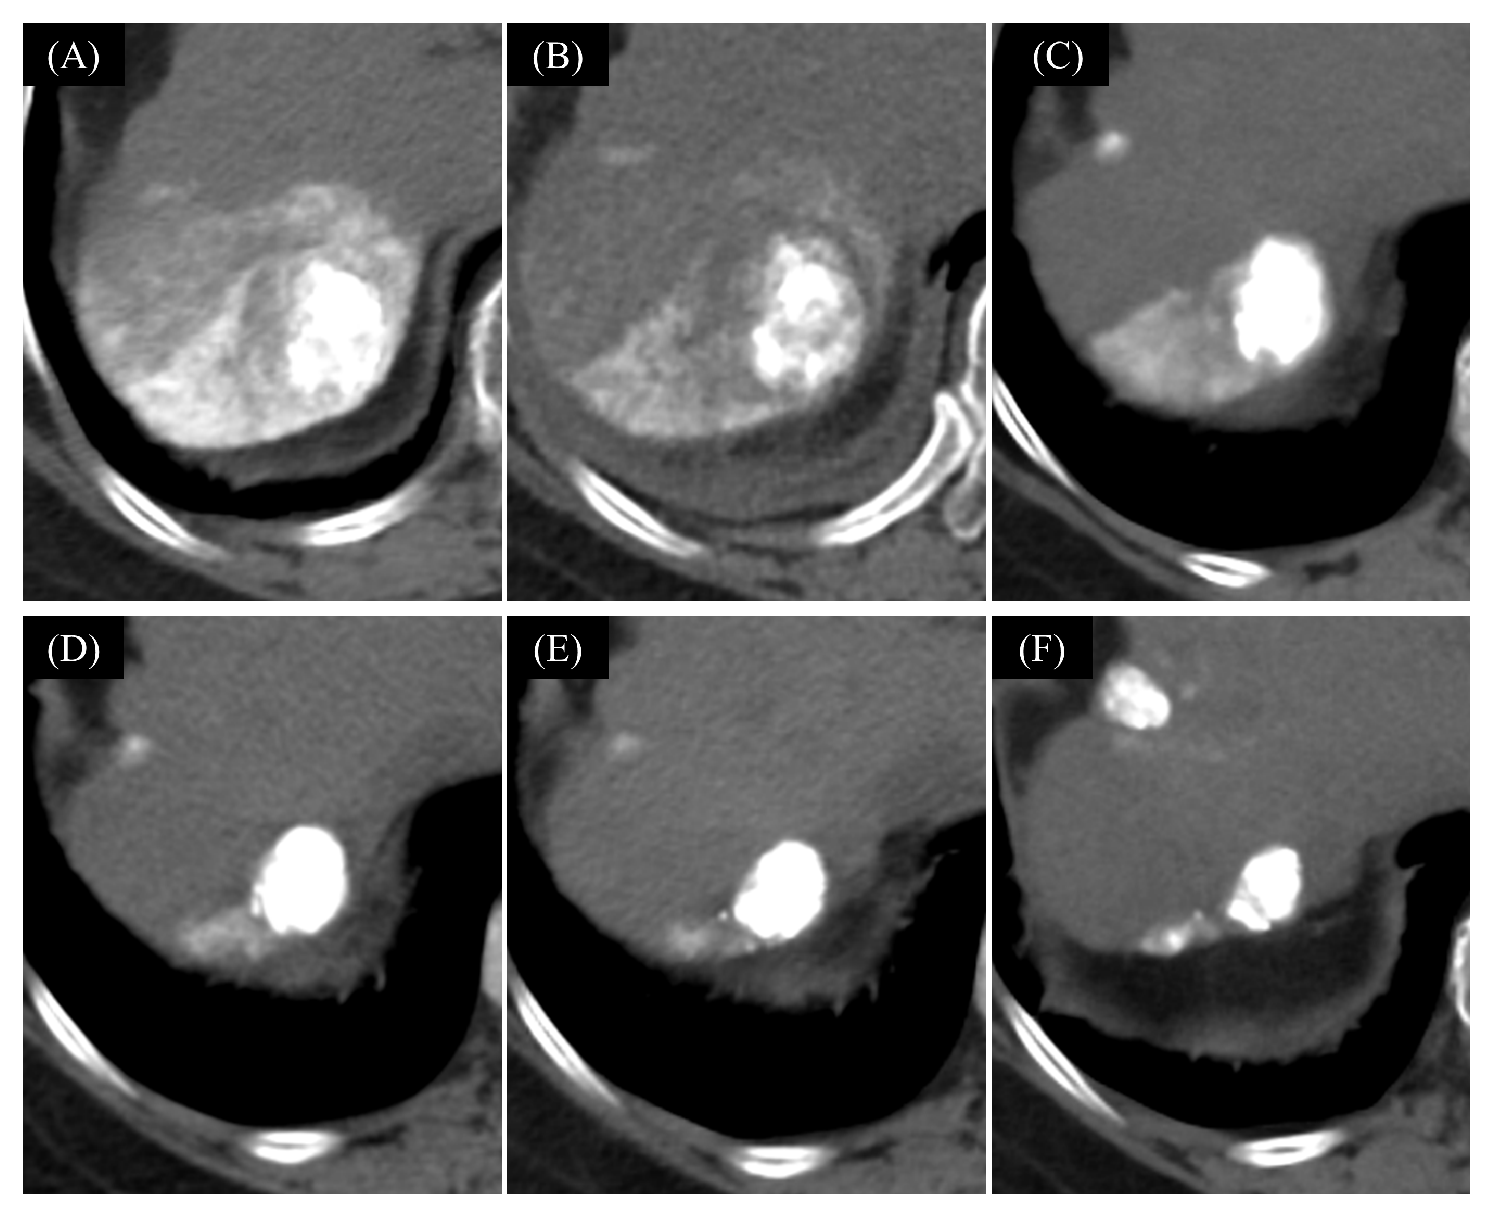

- Tachiiri, T.; Nishiofuku, H.; Maeda, S.; Sato, T.; Toyoda, S.; Matsumoto, T.; Chanoki, Y.; Minamiguchi, K.; Taiji, R.; Kunichika, H.; et al. Vascular Normalization Caused by Short-Term Lenvatinib Could Enhance Transarterial Chemoembolization in Hepatocellular Carcinoma. Curr. Oncol. 2023, 30, 4779–4786. [Google Scholar] [CrossRef]